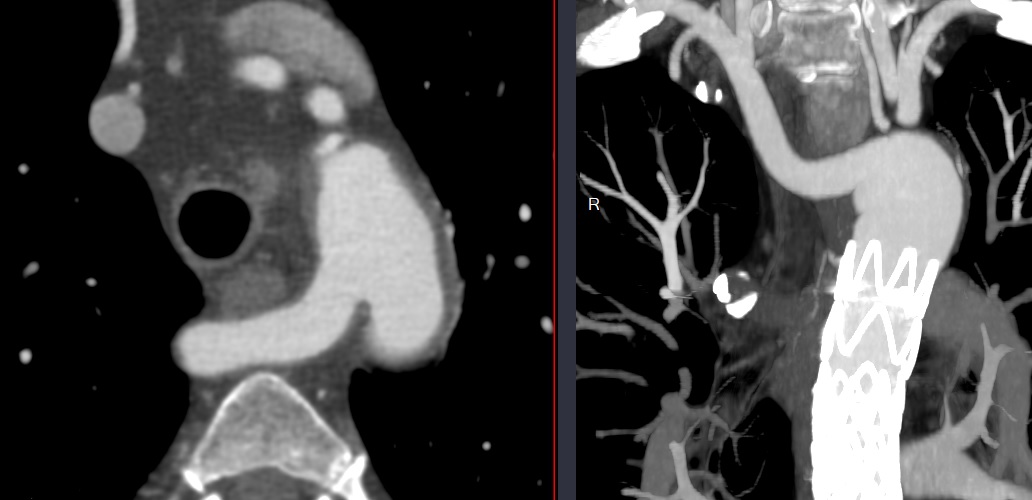

Arteria Lusoria

- Synonyme: Arteria Lusoria

Artère sous-clavière droite aberrante

- La plus fréquente des anomalies

- Asymptomatiques ++

- Rarement: Dysphagia Lusoria (compression oesophage)

- Peut faire des diverticules de Kommerell (plus rarement que la gauche aberrante)